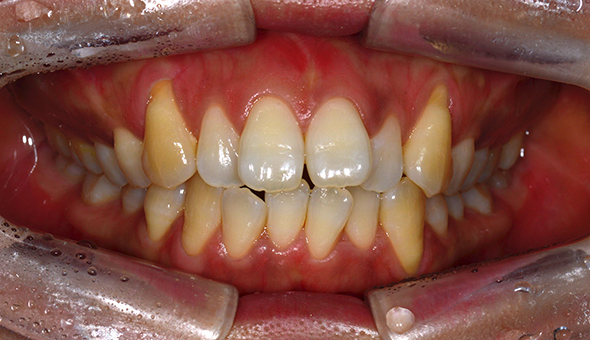

네비게이션 임플란트는 3D CT를 통해 입체 영상으로 정확한 수술 계획을 세우고, CT자료를 기반으로 구강에 끼우는 보조장치를 제작하여 잇몸 절개없이 작은 구멍을 뚫어 임플란트를 식립하여, 잇몸을 절개하는 수술방법보다 통증과 출혈이 적어 비교적 회복이 빠르게 나타납니다.